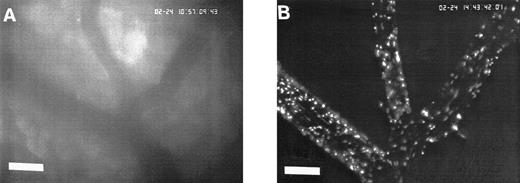

Sequence of photographs documenting I/R-induced platelet-endothelial cell interactions in vivo. Using IVM, rhodamine-6G–labeled platelets are visualized within 3 postcapillary venules before ischemia (A), as well as following 90 minutes of ischemia and 30 minutes of reperfusion (B). Few platelets adhere to the venular endothelium before I/R (A); the majority passes the vessel segment without interacting with the endothelial surface. In contrast, a large number of platelets are seen interacting with the endothelium 30 minutes after reperfusion (B). Monitor magnification 450×; bars represent 50 μm.